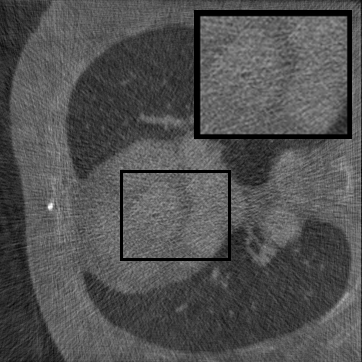

Figure 2: Qualitative inpainting results on TomoBank (lines 1 to 2) and LoDoPaB (lines 3 to 4) with random mask (ratio = 0.8) at 1024×\times1024 resolution. Odd columns and even columns show the sinograms and reconstructed images, respectively.

Inpainting Quality. Tab 2 summarizes accuracy results. At 2048×\times2048 resolution, HiSin achieves the best performance among all baselines while remaining memory-efficient, demonstrating its ability to extend high-quality inpainting to resolutions where other diffusion models fail. At 1024×\times1024, HiSin delivers accuracy comparable to its computation-intensive counterpart RePaint, showing that our optimizations do not compromise fidelity at moderate scales. Compared to DiffIR and HiDiffusion, HiSin consistently achieves higher SSIM and PSNR across mask ratios, with improvements up to +0.03 SSIM and +1.8 dB PSNR. Fig 2 visualizes sinogram inpainting and reconstructed images, where HiSin produces nearly indistinguishable results from RePaint. These findings confirm that HiSin fundamentally extends diffusion-based inpainting to 2048×\times2048 resolution in a more memory- and runtime-efficient manner.